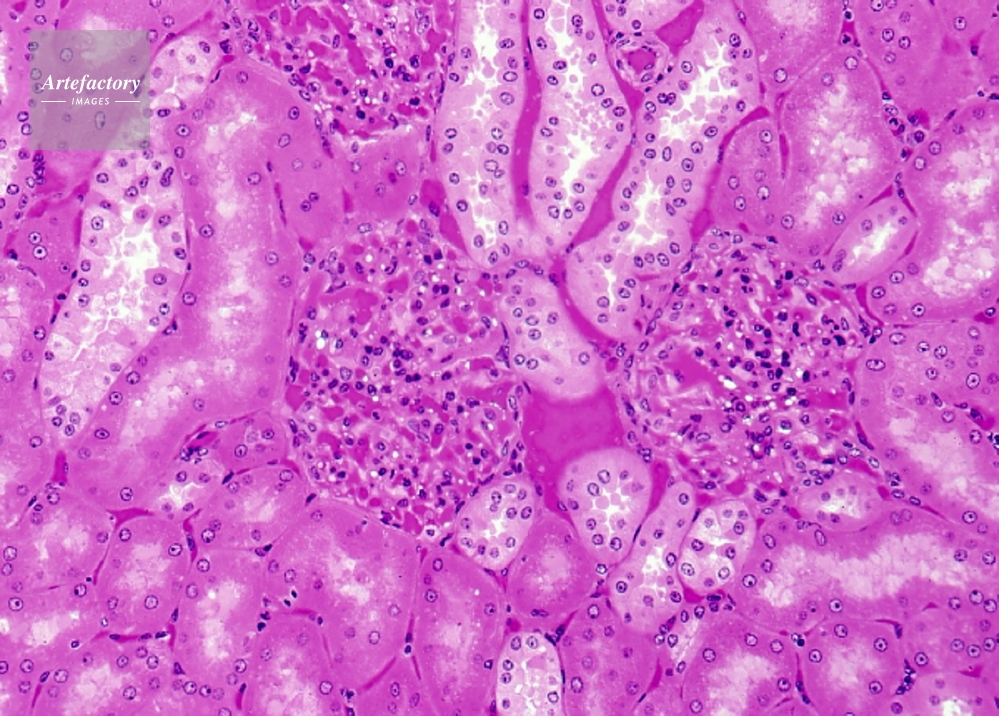

| 作品タイトル | サル 腎臓(腎小体、マルピーギ小体) | モデルリリース | なし | |

| キャプション | ヘマトキシリン・エオシン染色、長辺55mmの場合 80倍 | 制限事項 | こちらはポジのみの画像です。貸出中につきご提供できない場合はご了承ください。 | |